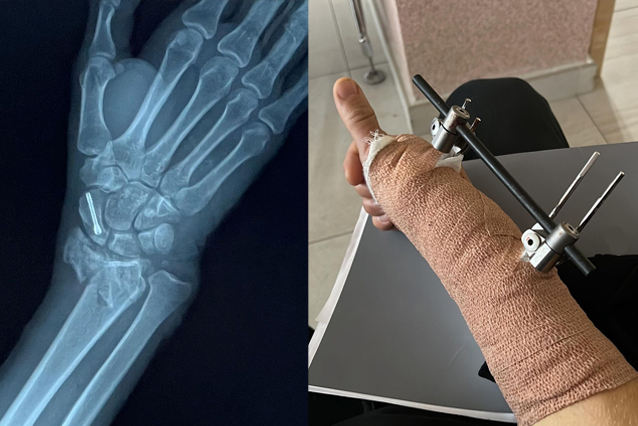

Při jednom skoku si přivodil otevřenou zlomeninu zápěstí. Po ošetření na místě ho organizátoři převezli do místní nemocnice, kde musel podstoupit okamžitou operaci. V tu chvíli již byl v kontaktu s naší asistenční službou, která nemocnici dala garanci proplacení operace.

Po úspěšné operaci náš tým organizoval pravidelné prohlídky na místě a asistenční lékaři vyhodnocovali situaci, kdy bude možné Jakuba převézt zpět do České republiky. Původně jsme chtěli do Mexika poslat zdravotní sestru, která by převoz doprovázela. Po domluvě s Jakubem jsme mu nakonec zařídili dřívější zpáteční let v business třídě, aby měl dostatek prostoru a omylem mu někdo do sešroubované ruky nevrazil.